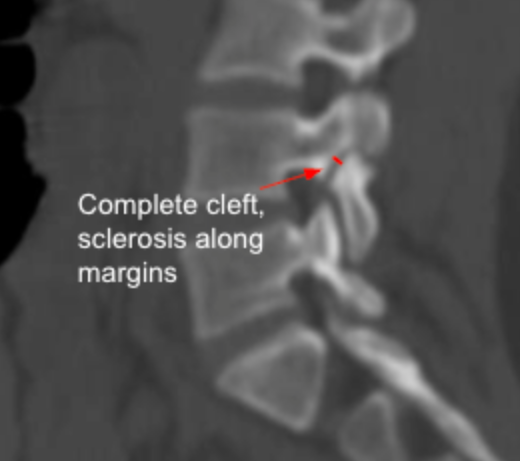

Pars Interarticularis Defects